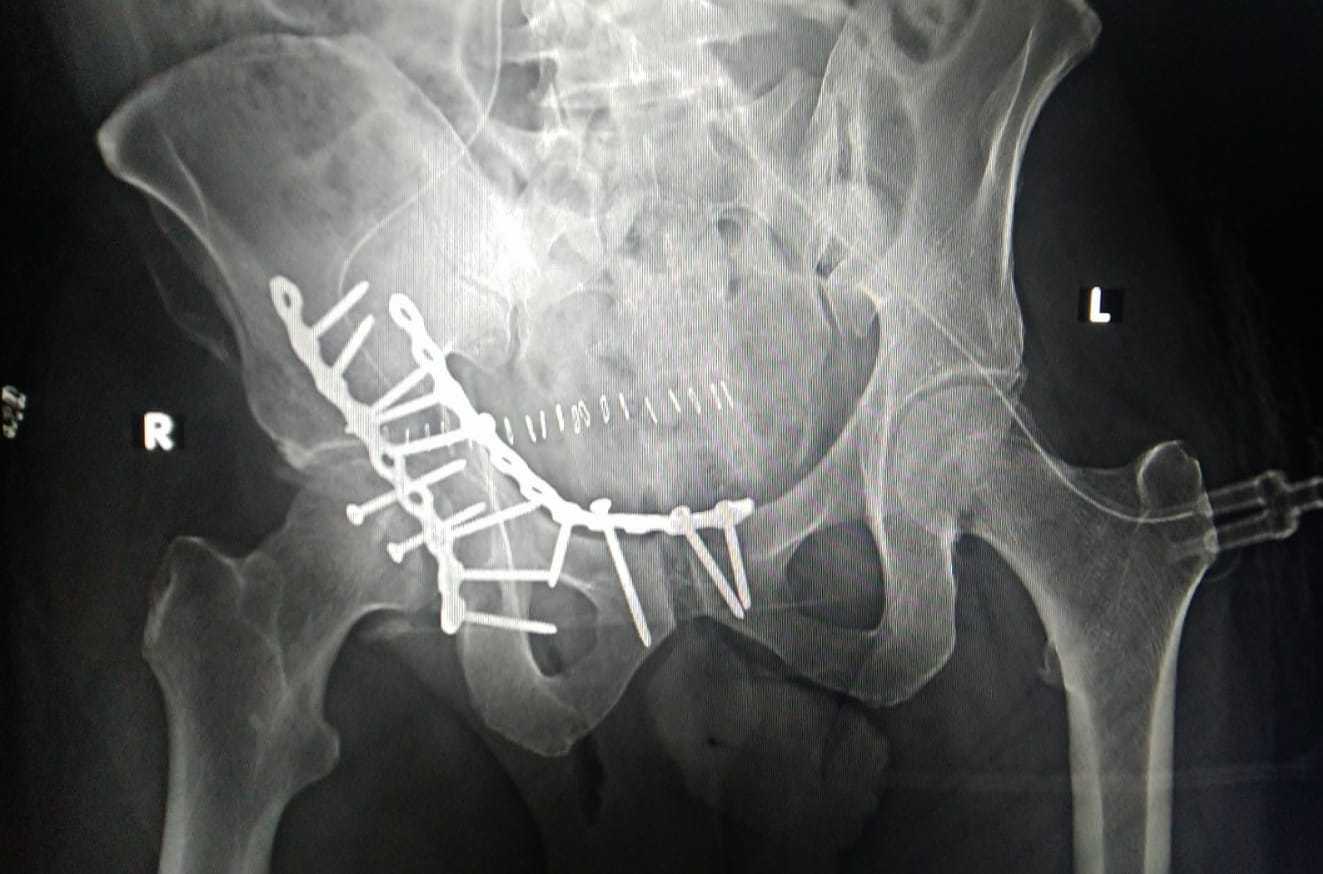

PELVI ACETABULARY INJURY